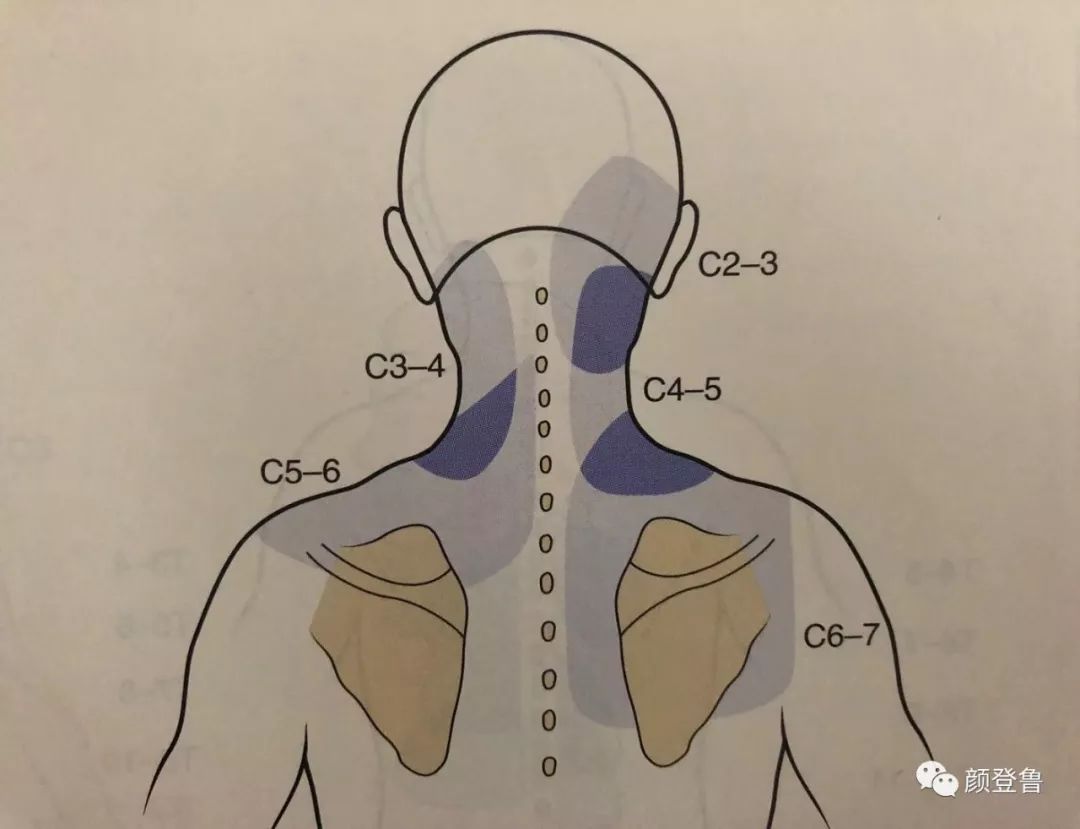

颈椎的椎间盘源性轴性痛,是指在颈椎退变的基础上,椎间盘变性和慢性损伤导致颈肩部疼痛、僵硬、头晕头痛、颈部活动不适等症状。

颈椎的盘源性疼痛,与椎间盘的纤维环、后纵韧带、硬脊膜等表面分布的窦椎神经受刺激后产生疼痛有关。椎间盘表面有丰富的神经网和游离神经末梢,椎间盘纤维环后壁受到双侧和邻近节段窦椎神经的重迭支配。

在颈部的窦椎神经主干直接与椎间盘纤维环的后面相邻,在颈部的椎间盘向后外方向突出时,可直接刺激窦椎神经的主干。窦椎神经有交感神经的分支加入,经椎间孔进入椎管。

窦椎神经分布于脊膜、椎管、椎管内所有组织、椎间关节囊、椎骨的韧带及脊髓的血管都有窦椎神经分布,在后纵韧带、硬脊膜前部和神经根袖内分布最密集。